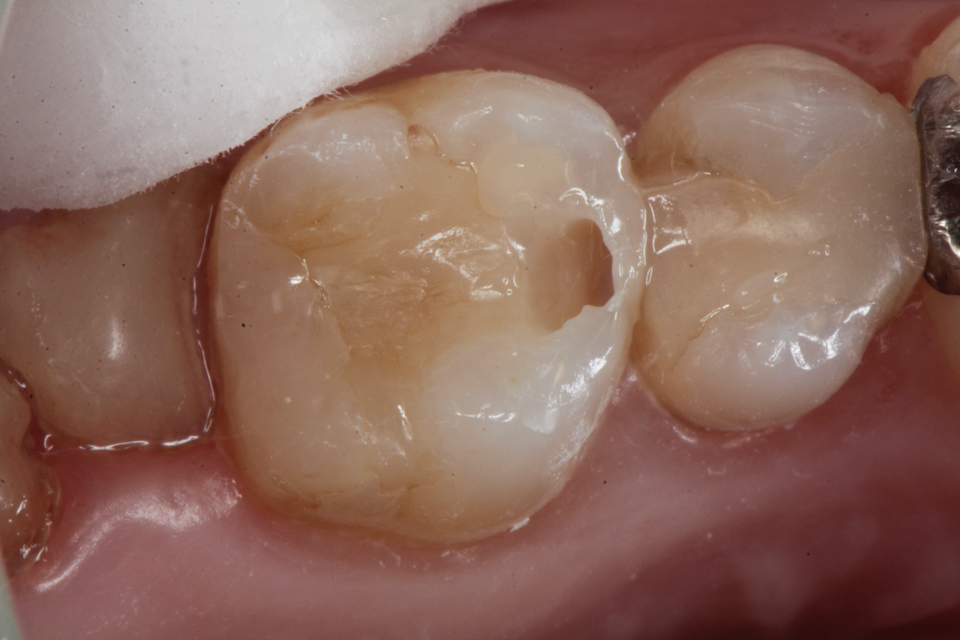

虫歯は金属の錆や腐食と同じ1.42 2025.11.10

虫歯は金属の錆や腐食と同じ1.41 2025.06.05